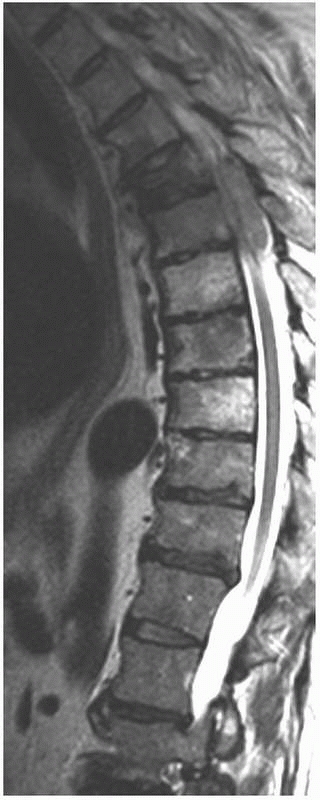

involvement of the spine is loss of a pedicle on an anteroposterior

view. MRI can be used to differentiate an osteoporotic compression

fracture from one caused by a malignant lesion.102

When there is complete replacement of the vertebral segment, multiple

vertebral body lesions, pedicle involvement, and an intact

intervertebral disk, metastatic disease is most likely (Fig. 20-12).

FIGURE 20-12

This sagittal T2-weighted MR image without fat suppression in a 57-year-old man with multiple myeloma shows a thoracic vertebral compression fracture with marrow replacement in multiple vertebral bodies and an associated large epidural lesion. |